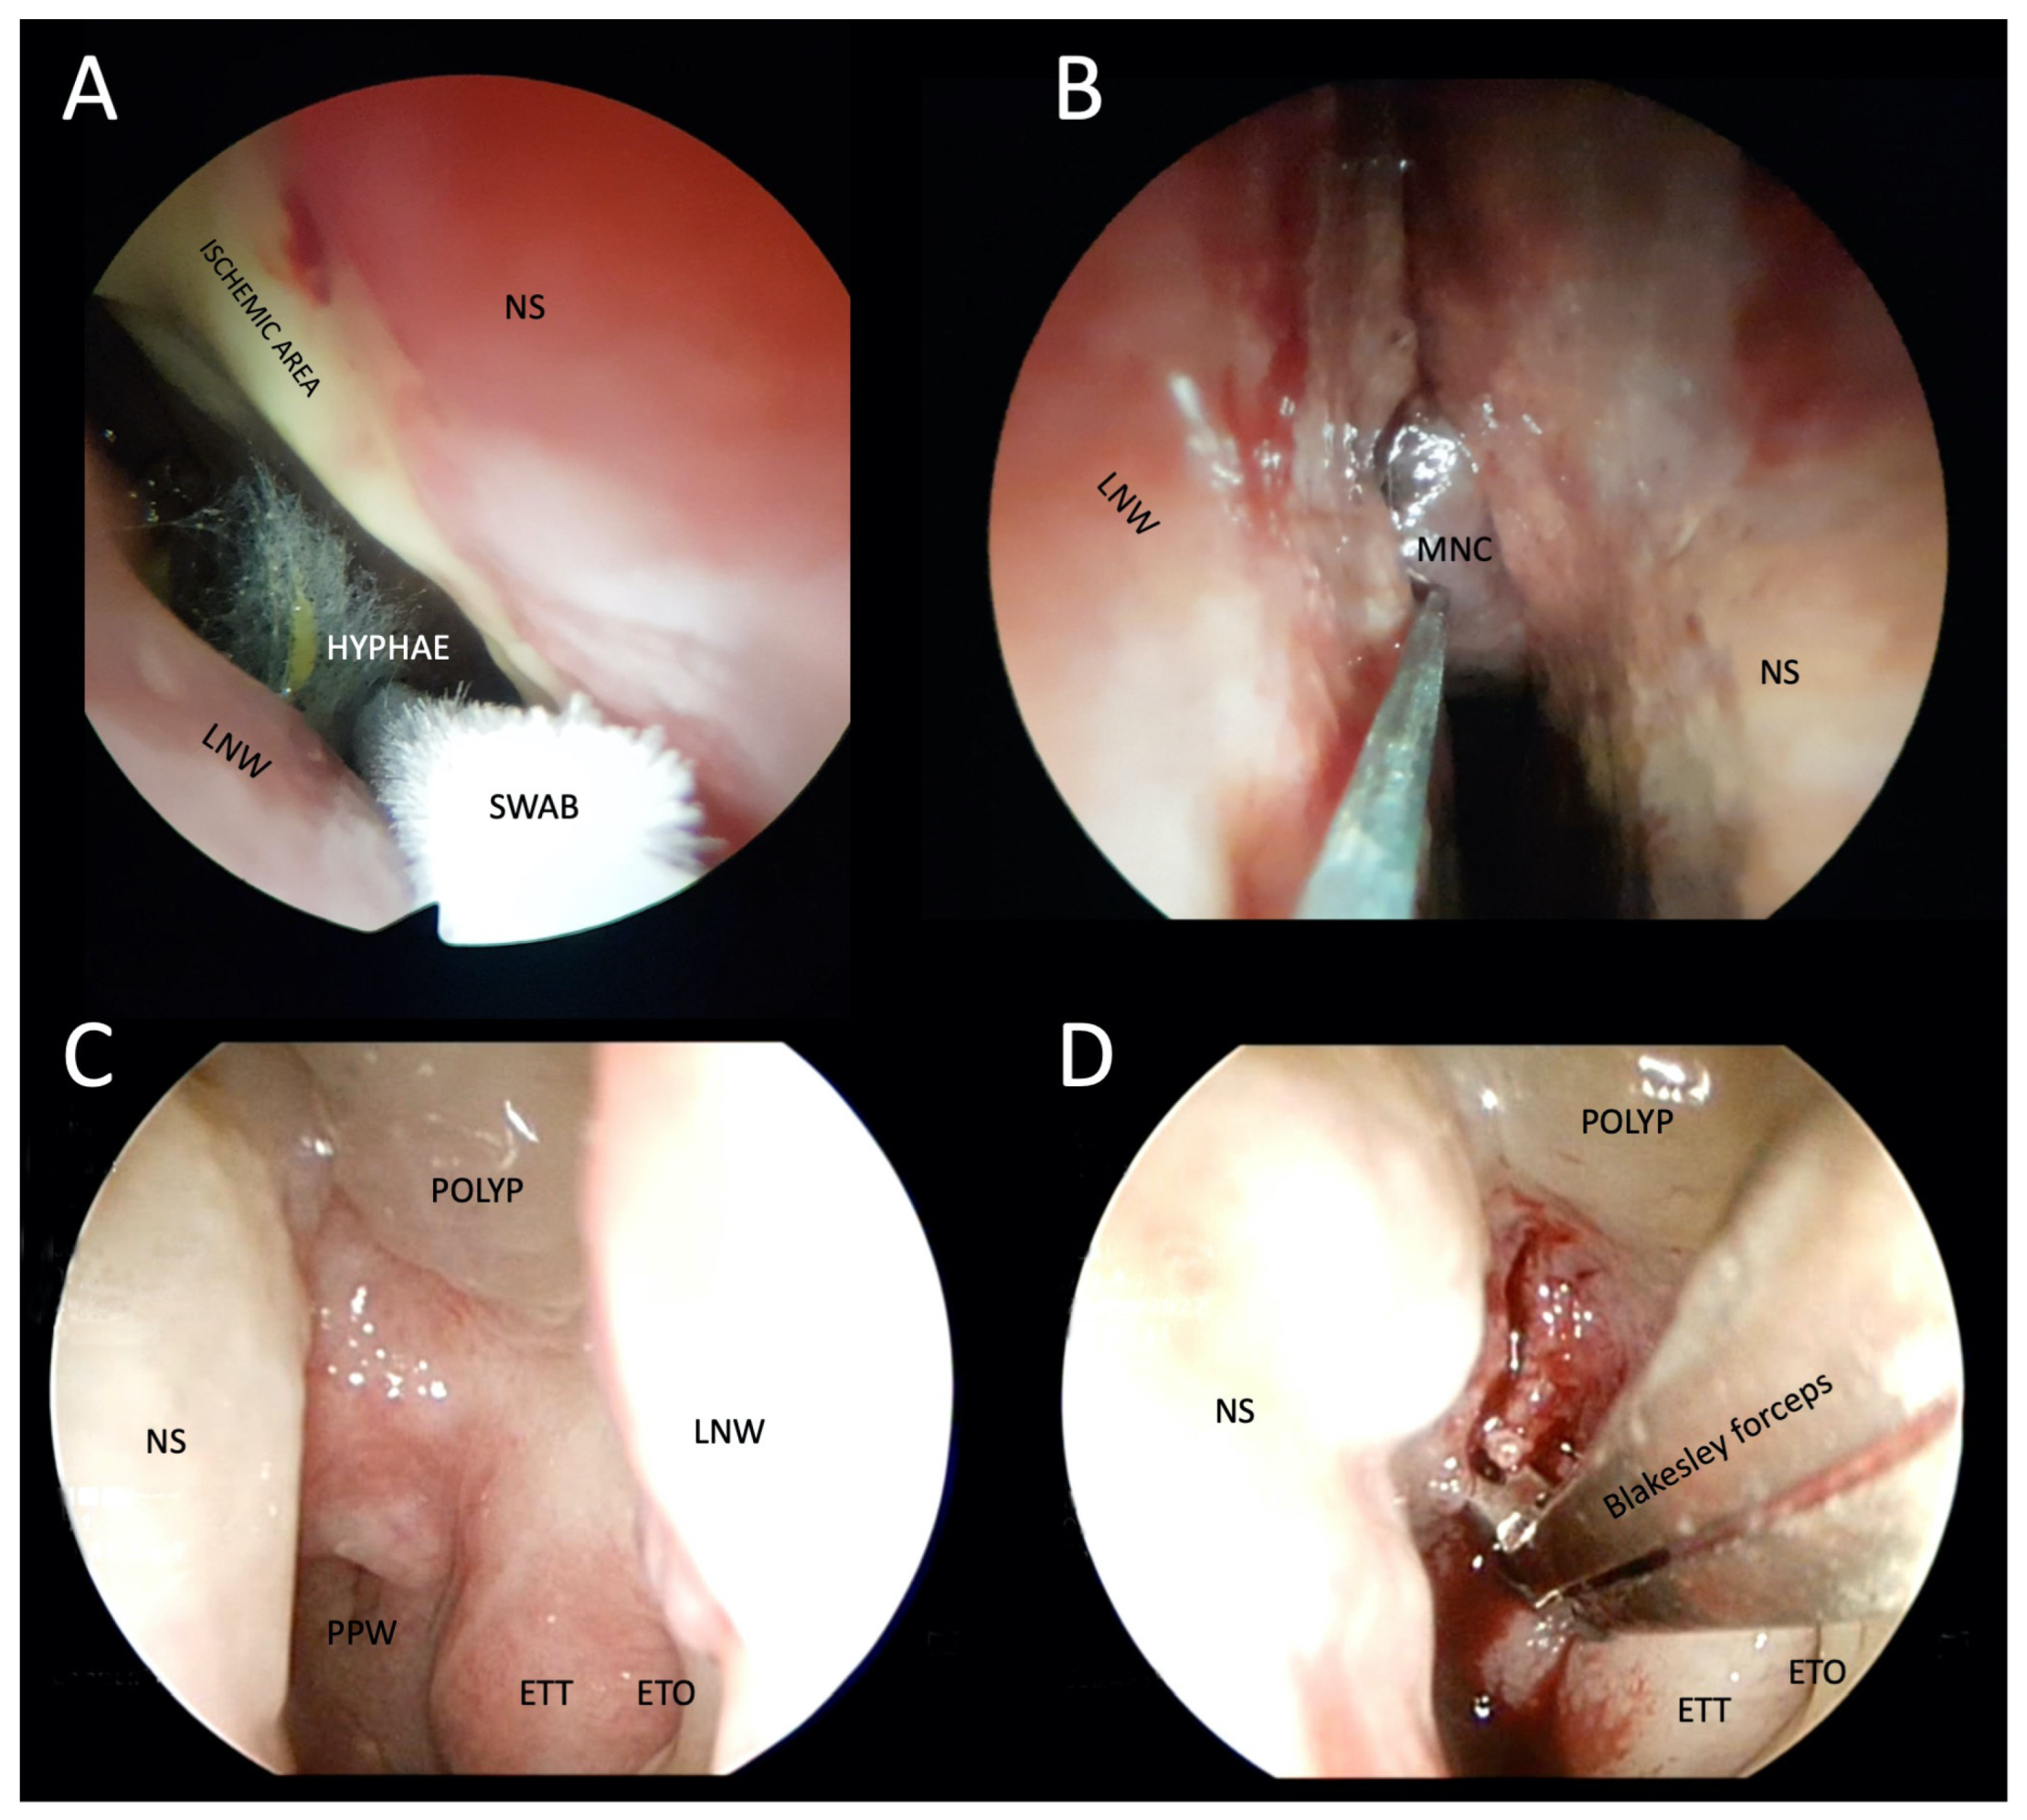

Figure 5.

Photographs of transnasal endoscopic collection of pus and tissue specimens for microbiological and histopathological examination in patients with suspected atypical skull-base osteomyelitis. (A,B) Swabs were taken from a patient with rhino-orbital-cerebral mucormycosis. Fungal hyphae are visible in the right nasal cavity, ischemia of the nasal septum, and the middle nasal concha necrosis, which has a blackish appearance (i.e., black turbinate sign). (C) Thickened epipharyngeal tissue with normal mucosa in a patient with atypical fungal skull-base osteomyelitis. (D) Deep biopsy after epipharyngeal incision. LNW: lateral nasal wall; NS: nasal septum; MNS: middle nasal concha; PPW: posterior pharyngeal wall; ETT: eustachian tube torus; ETO: eustachian tube orifice.